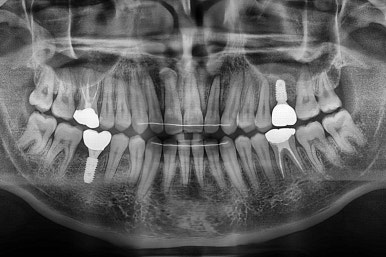

왼쪽이 치료 전, 오른쪽이 연산동임플란트 치료 후 X-ray 사진입니다.

초진 시의 입안 모습입니다.

어금니가 빠져서 결손치아가 있고 치아 사이에 틈새도 있어서 교정치료도 함께 원한다고 내원해 주셨어요.

사진에서 보시는 바와 같이 윗니 1개, 아랫니 1개의 결손 부위가 보입니다.

윗니 어금니 중에는 신경치료를 마무리 못하고 임시재료로 메꿔뒀던 부위도 보이고요.

교정치료도 종료 되었고 연산동임플란트 잘 완성이 되었어요.